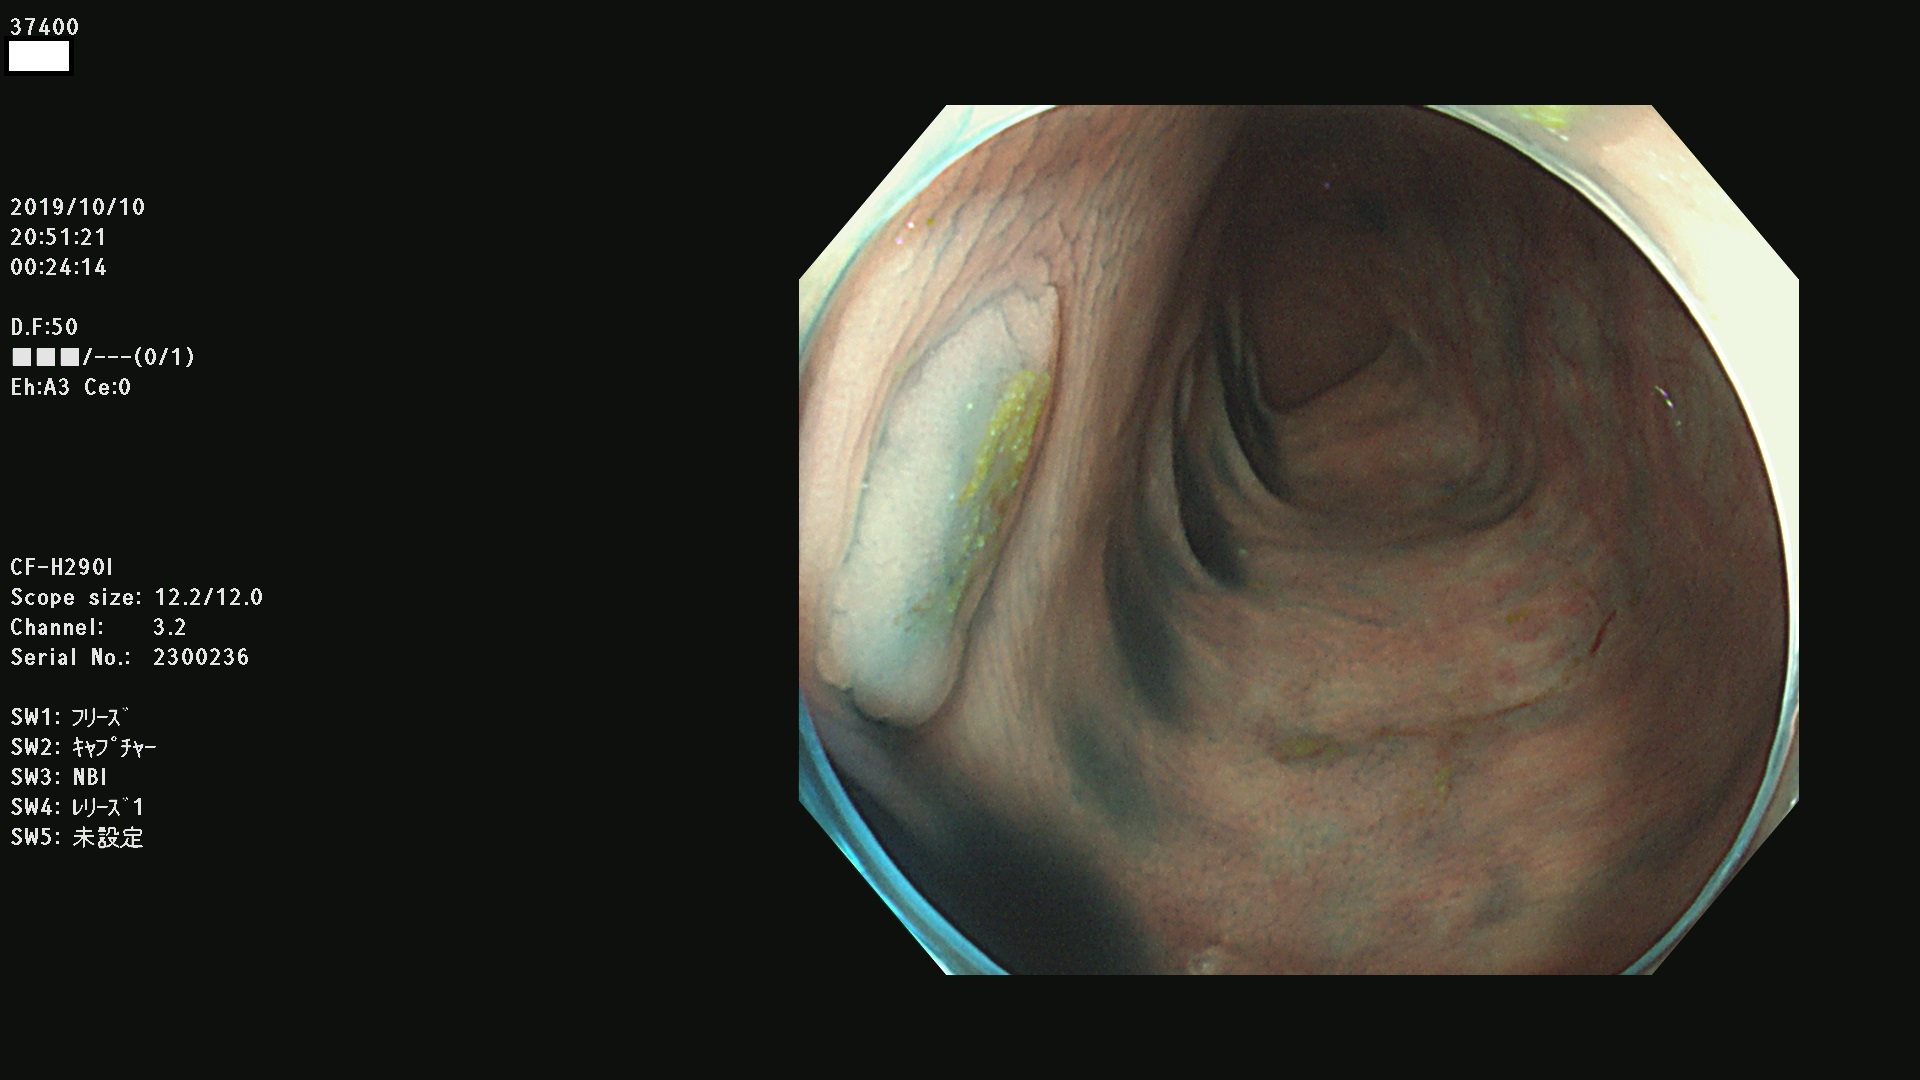

37400(SSAPのみ) 37401 37403 37404 37405 37406 37407 37408 37410 37411 37412 37413 37415 37416 37417 37420 37423 37424 37425 37426 37428 37430(SSAPのみ) 37432 37433 37434 37435 37436 37437 37438 37439 37440 37442 37443 37444 37447 37448 37449 37450 37451 37452 37455 37456 37457 37458 37459 37460 37461 37462 37464 37467 37468 37469 37470(SSAPのみ) 37471 37472 37474 37476(SSAPのみ) 37477 37478 37480 37481 37482 37483 37485 37486 37487 37488 37489 37490 37491 37492 37493 37494 37497 37499

発見困難で危険性の高い平坦型病変(上記100名より抽出)